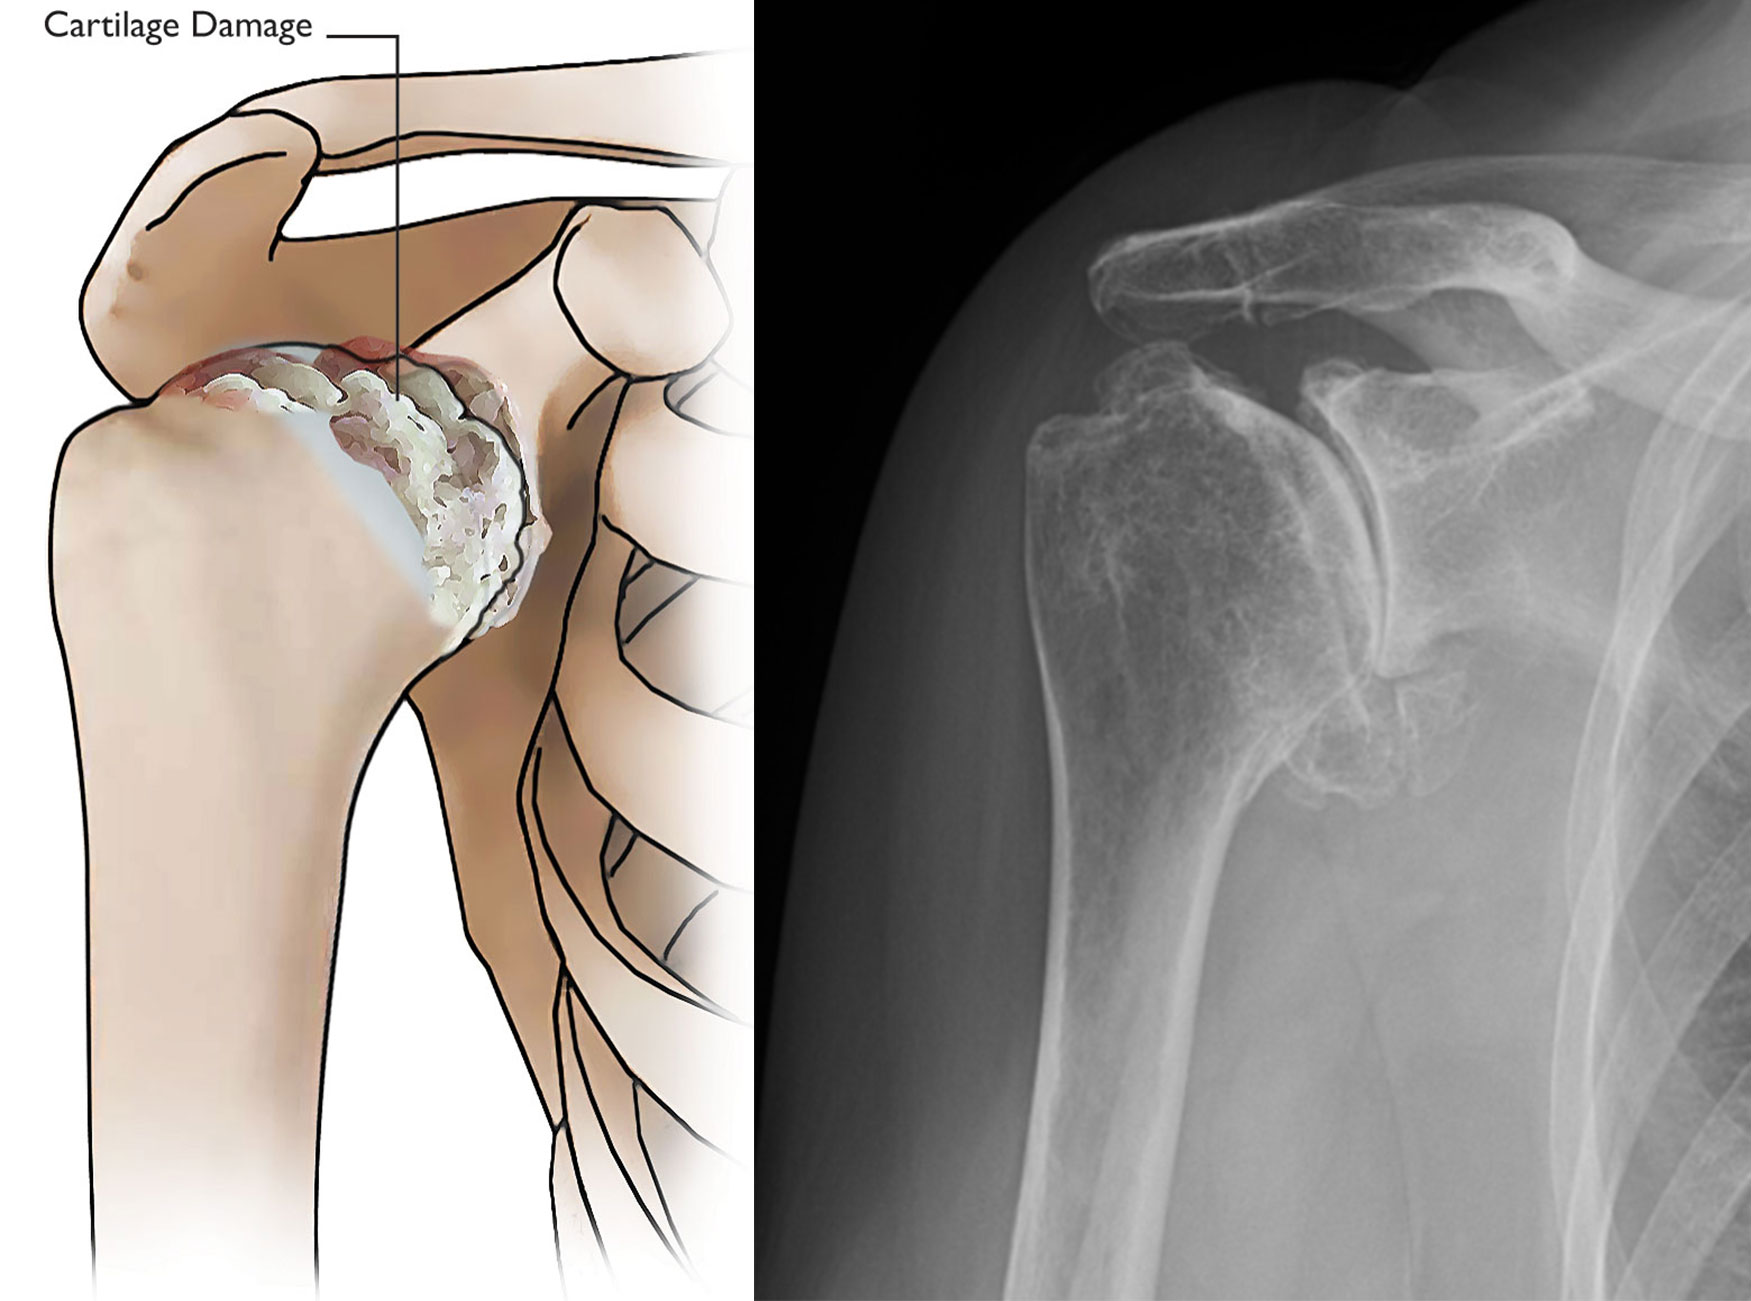

Osteoarthritis of the shoulder

Osteoarthritis of the shoulder. As the cartilage that covers the ends of the bones wears away, it can result in bone rubbing on bone and produce painful bone spurs.

X-ray of osteoarthritis of the shoulder

(Left) An X-ray of a healthy shoulder joint. (Right) Osteoarthritis of the shoulder. Note the decreased joint space (arrow).